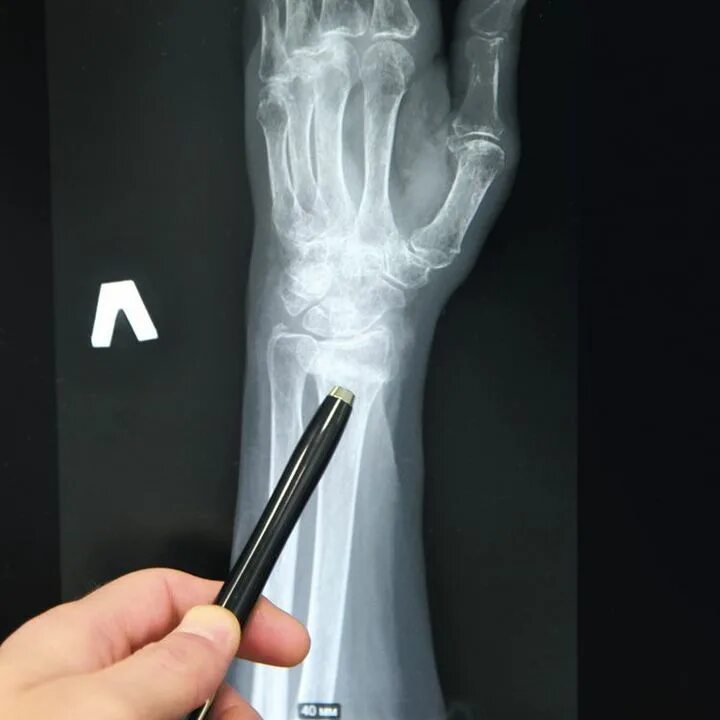

Перелом лучезапястного сустава лечение